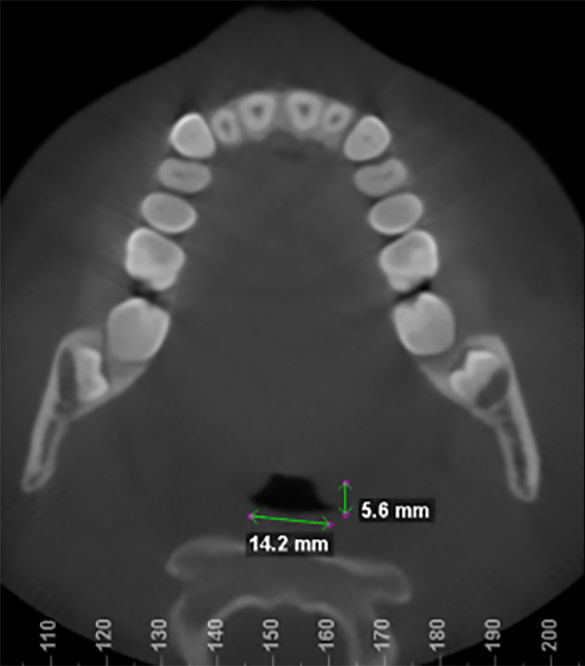

Before and after images of patient after 9 months of successful treatment: